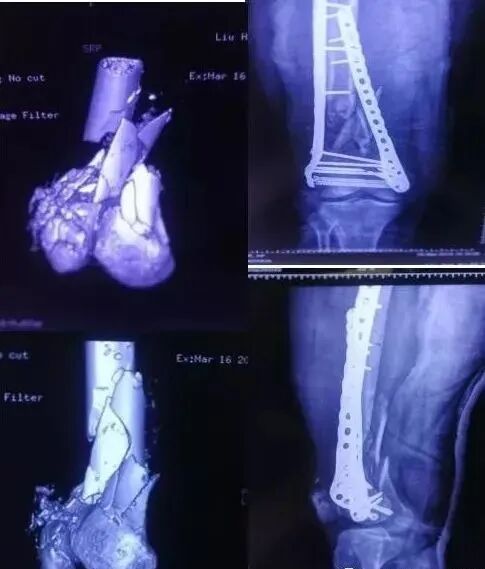

7)胫骨远端(pilon,踝部)

图片

• pilon骨折,高能损伤,6-8h肿胀未形成,可以急诊做,手术时间<3小时。

• 10-14天,分步延期手术策略。

• 踝部骨折手术时机同样取决于皮肤条件。